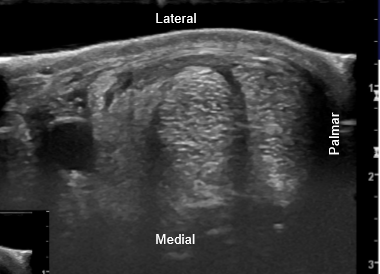

• does this show a manica flexoria tear or is it normal?

normal

tear